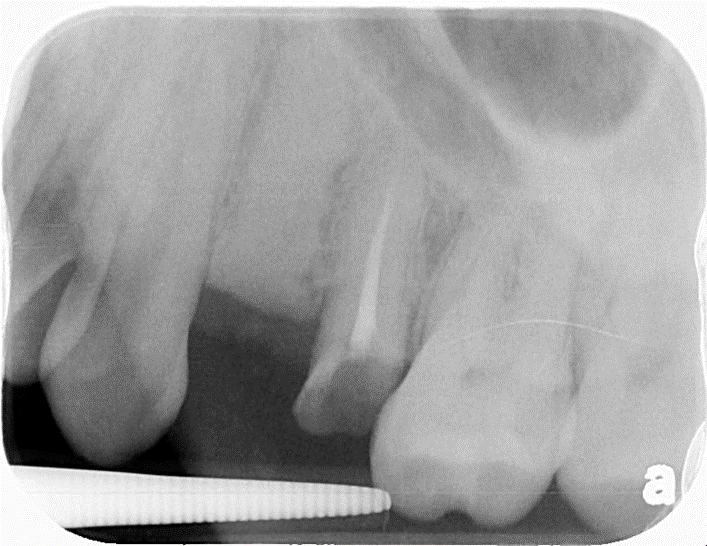

治療前,左下第一大臼齒嚴重蛀牙

治療前,蛀牙至牙根處